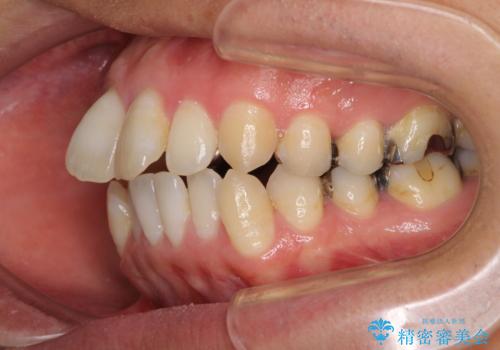

- 前歯のデコボコと、上顎前歯の突出感を気にして来院された患者様です。

通常の咬み合わせ位置と比較して、上顎の歯列が全体的に前方にある状態で、上下前歯の前後方向の位置に著しい差がありました。

上顎奥歯付近にアンカースクリューを用い、上顎歯列全体の後方移動と、大臼歯圧下を促し、前歯の上下関係を改善することとしました。

奥歯には目立つ銀歯が多くあるので、矯正治療後には下顎の銀歯をセラミッククラウンやセラミックインレーにより、補綴・修復治療することとしました。